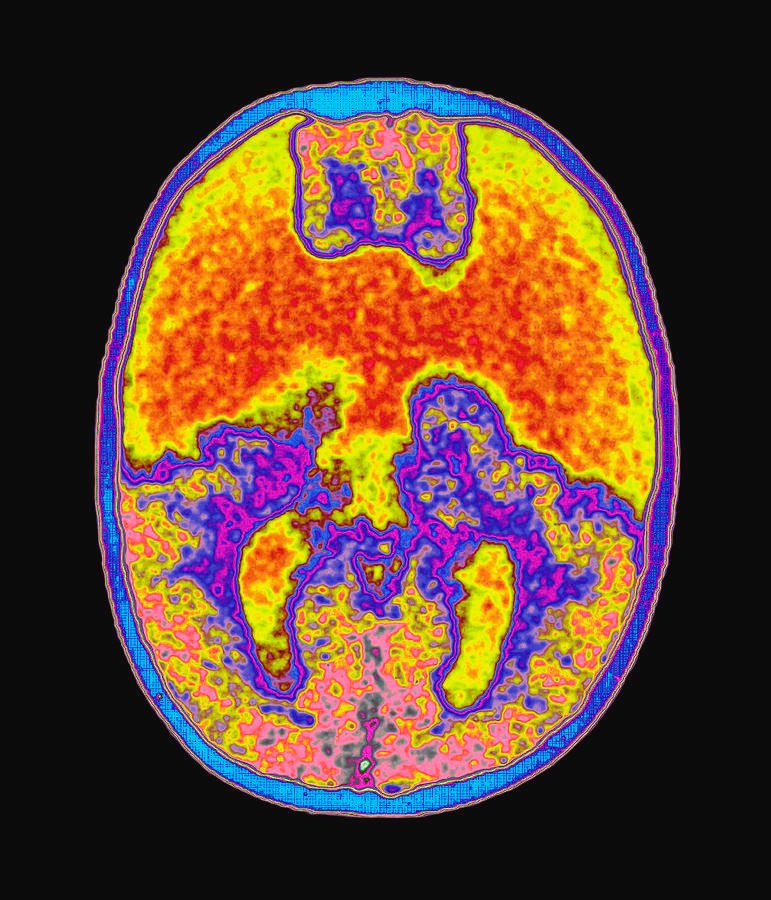

Your brain has been fooling you your entire life.

This Nobel Prize winner spent 40 years proving it.

After surviving the Holocaust, Daniel Kahneman became obsessed with understanding human behavior.

Together, they discovered our brains operate in two distinct modes.

They called them 'System 1' and 'System 2.'

This discovery would revolutionize economics, psychology, and how we understand human behavior.

System 1:

This is lightning-fast, intuitive thinking. That no-effort, automatic kind. It's how we make snap judgments.

System 2:

This is slow, analytical thinking.—used for complex problems & questioning assumptions. It takes mental effort.

System 1 is in charge 95% of the time.

And while this quick thinking helped our ancestors survive ("Is that a tiger?"), it creates massive blind spots in modern life.

These blind spots are called cognitive biases.